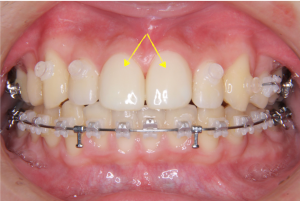

※矯正治療中の正面

上記の写真のように、ハーフリンガル矯正では、上の歯は内側に装置を装着するため、見た目には装置が付いていないように見えることがあります。

※矯正治療が進んだ際の口元の拡大写真

上の前歯2本の形にバランスの乱れがあるため、この時点ではまだ歯と歯の間にすき間が残っている状態です。